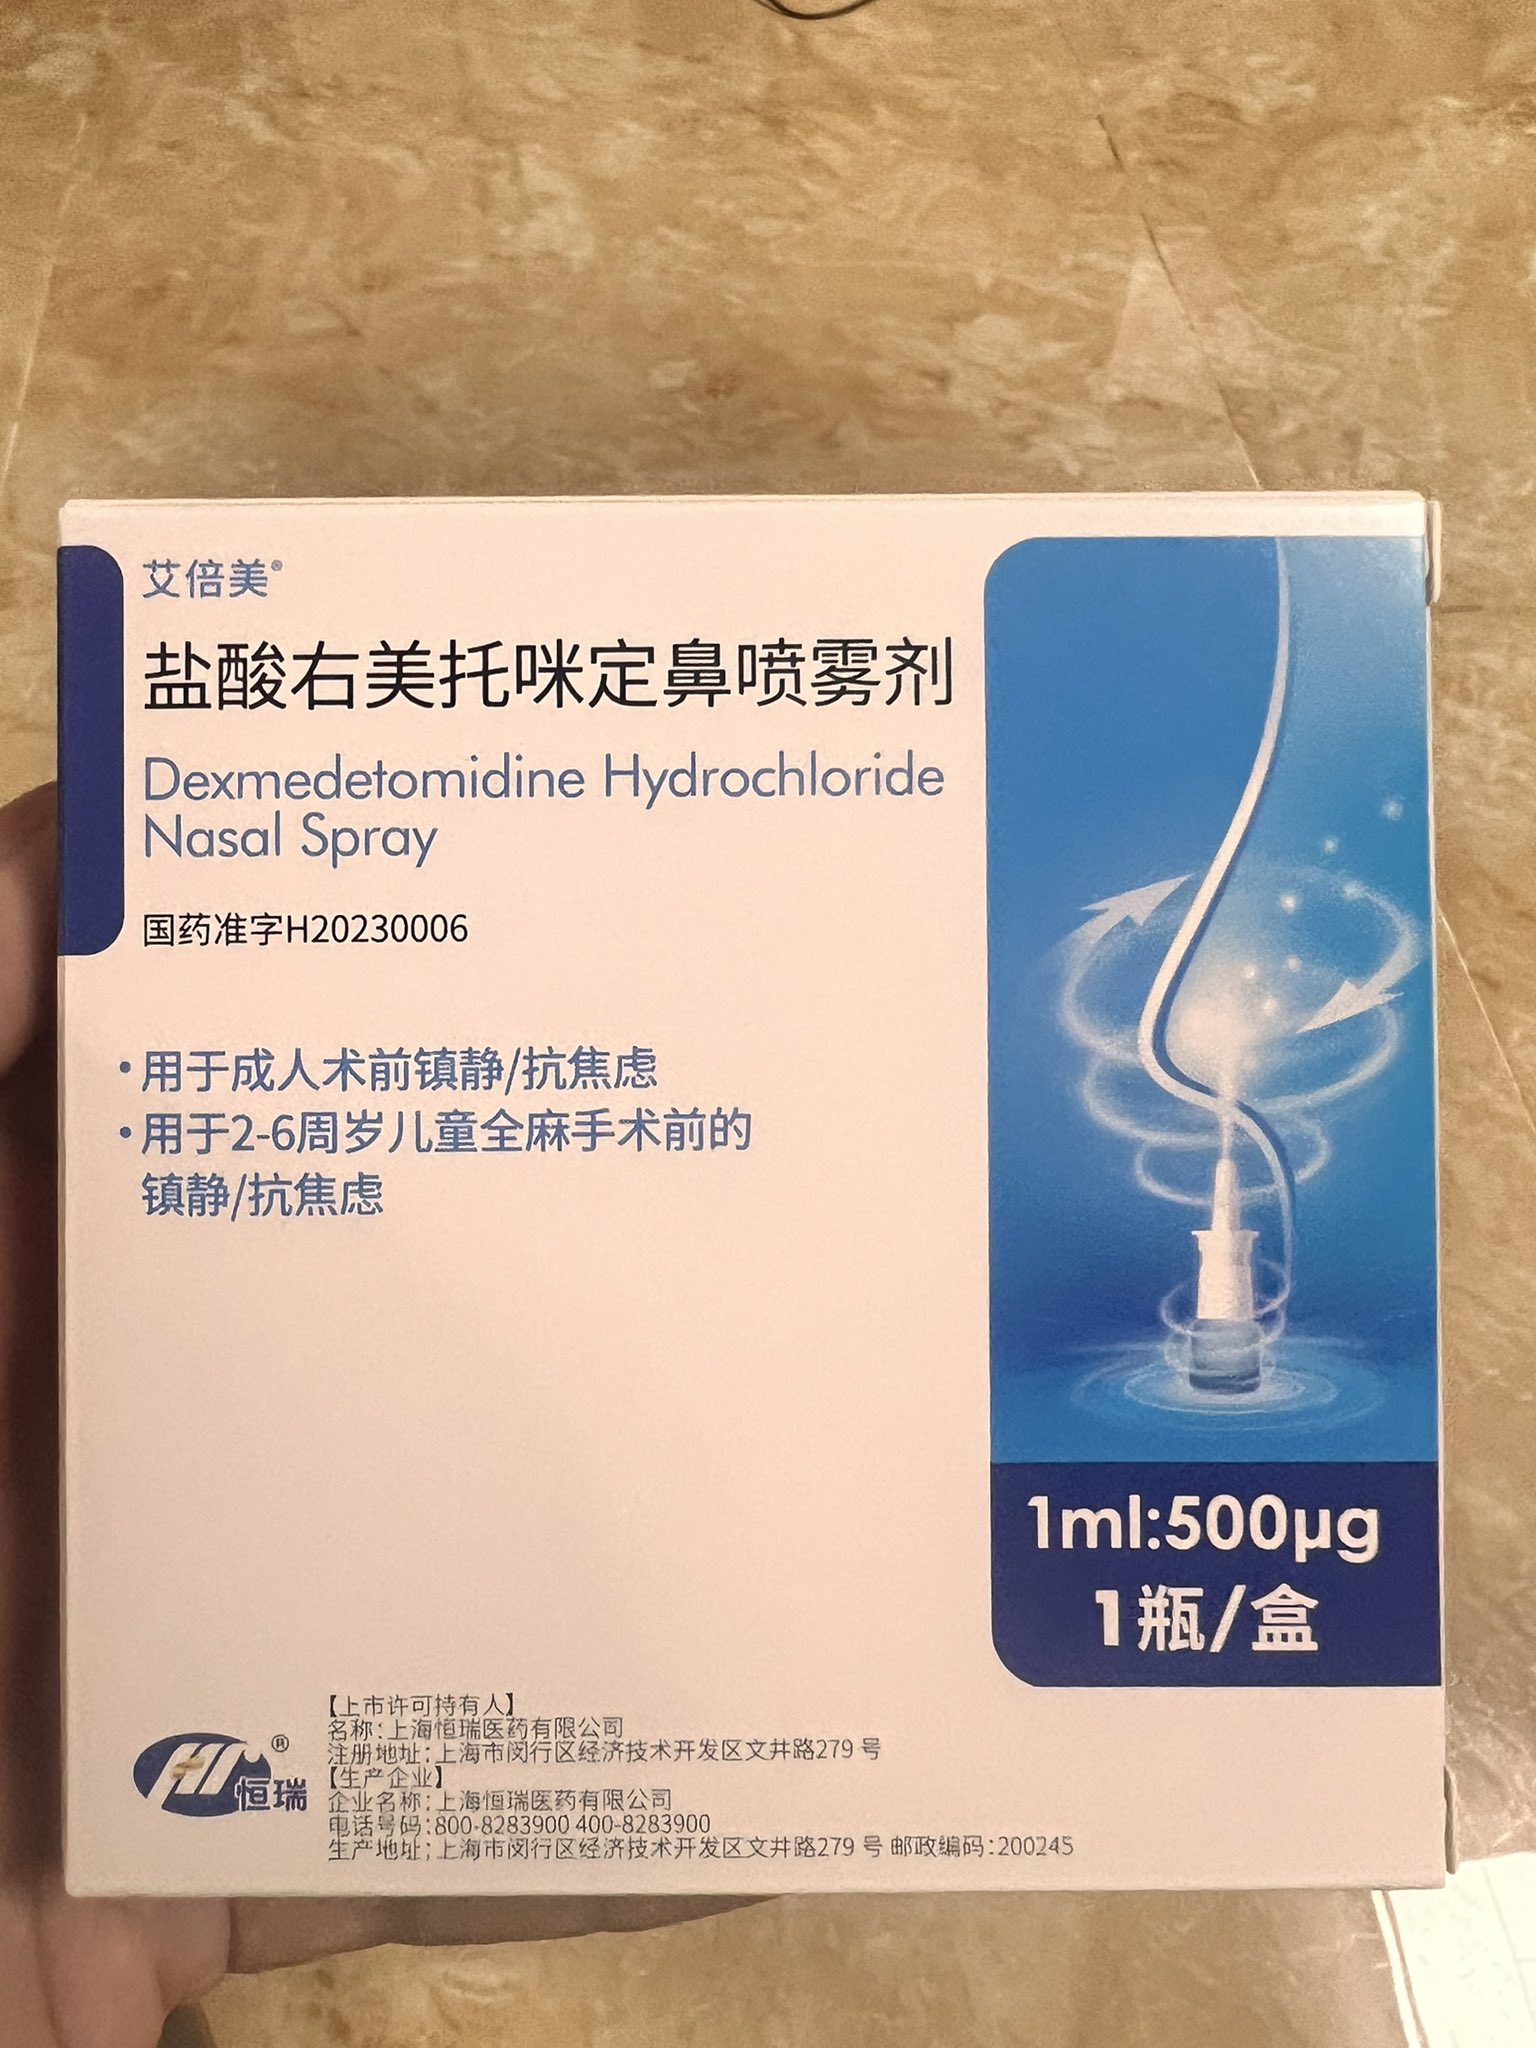

首先,从定义上讲,“反解离(anti-dissociative)”并不是一个标准的医学术语或者广泛认同的药理学分类。在正规资料,比如医学文献、维基百科、精神药理学教科书中,目前并没有“反解离药物”这个正式概念。

看上去像是为了描述某类特定效应而创造的术语(可能是nmda受体活性增强),用来对抗因NMDA受体拮抗剂(比如氯胺酮、DXM、PCP等)引发的解离体验(dissociation)。

那么更常见的是将其归入认知增强剂(cognitive enhancers),特别是改善认知连接性(connectivity)和现实感知(reality testing)的类型。

但其实在药理学上,单纯用“受体激动剂”来逆转“受体拮抗剂”的效应,有时会导致过度激活。

对于NMDA受体而言,过强的NMDA活化本身就与兴奋性毒性(excitotoxicity)和精神病样症状(psychotomimetic effects)有关,比如谷氨酸风暴可以引发严重的焦虑、妄想、乃至癫痫。

也就是说,简单地“激动-解除拮抗”在中枢神经系统是很危险的做法,尤其是对于易感个体(如有精神分裂素质的人)。

科学的处理方式一般是通过更细致的调节,比如微调NMDA/AMPA平衡、调节其他辅助途径(如GABA、5-HT、mGluR受体),而不是简单粗暴地用“NMDA增强剂”去顶回去。

而临床处理药物中毒中,其实医生更常用的做法是保守、支持性的治疗,比如补液,促进代谢,必要时镇静,以及监测生命体征防治并发症。

药物拮抗与受体激动之间,往往牵扯到的是复杂的适应性变化(receptor upregulation/downregulation),

不是简单的“给多一点刺激就能抵消”的关系